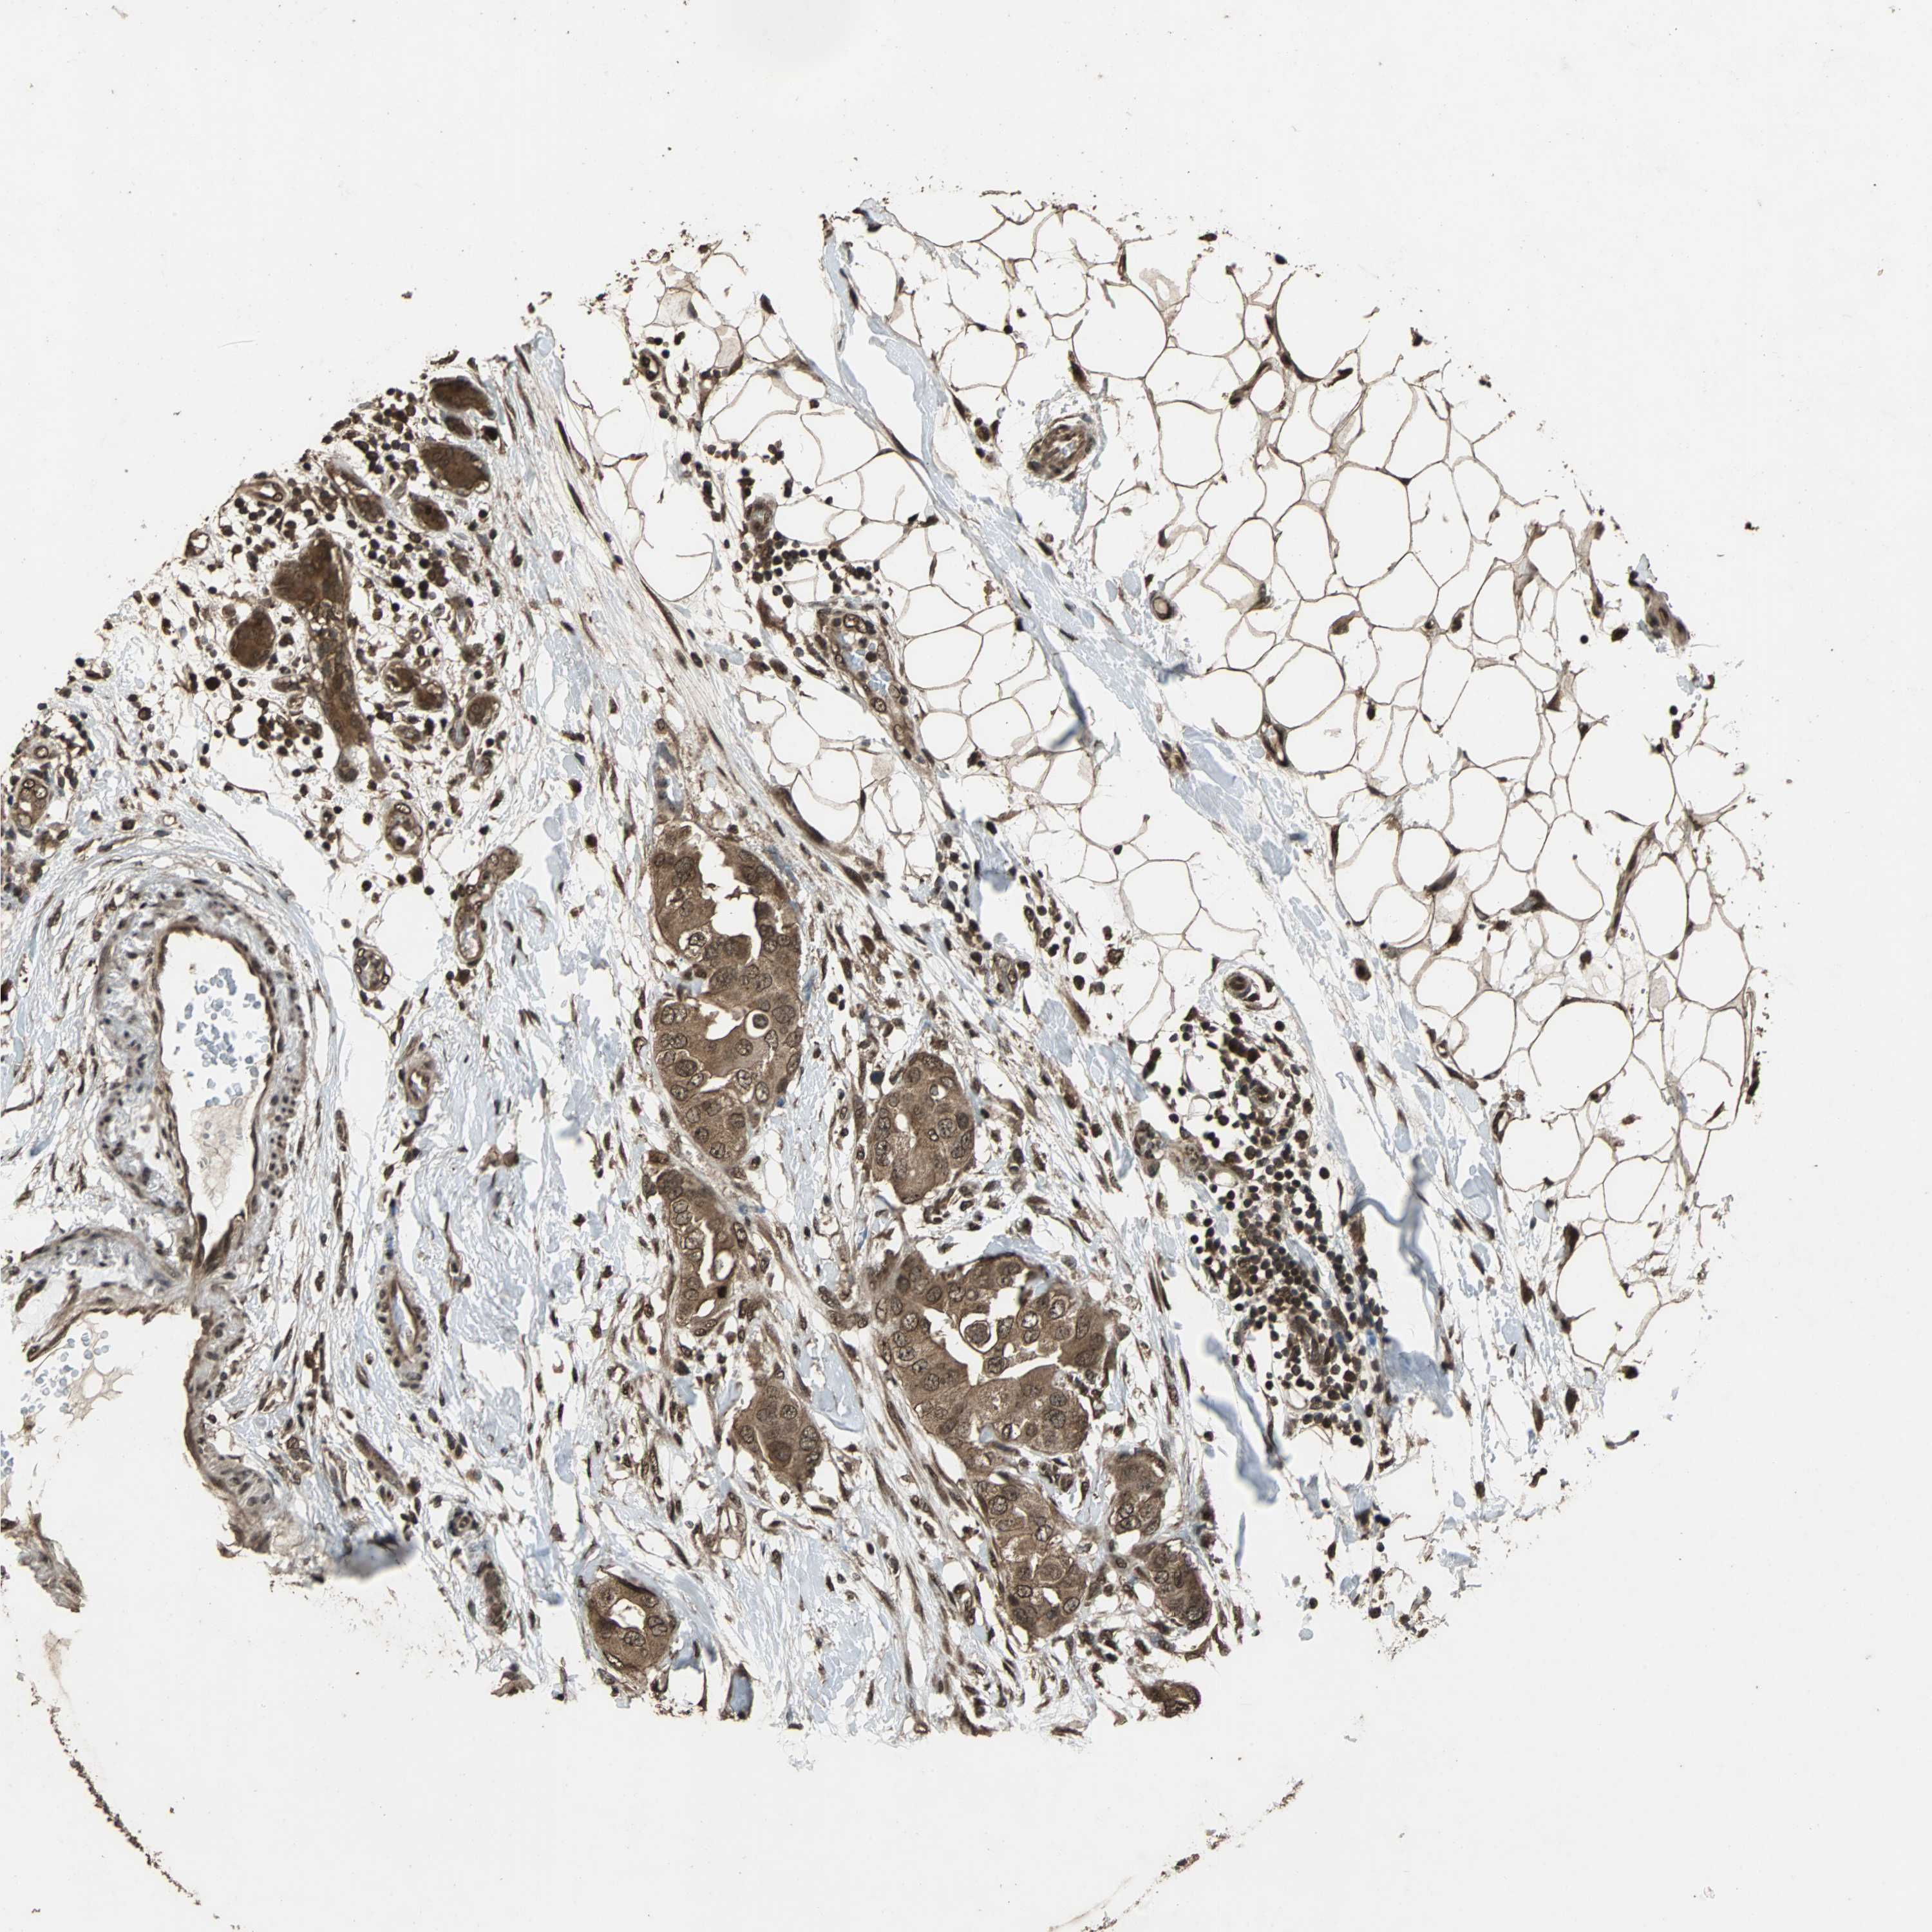

CANCER BREAST CANCER Show tissue menu

Breast cancer

Human cancer